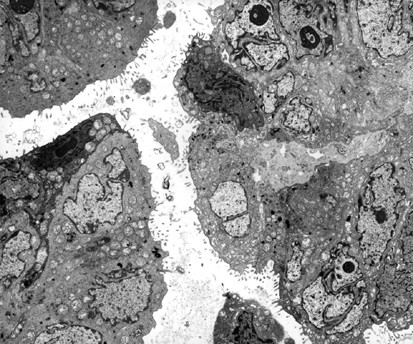

Figure 11

High-grade serous carcinoma. The nuclei are markedly irregular and often contain prominent nucleoli. The cell membranes are closely apposed and microvilli are restricted to the apical surface of the papillae (× 5000).